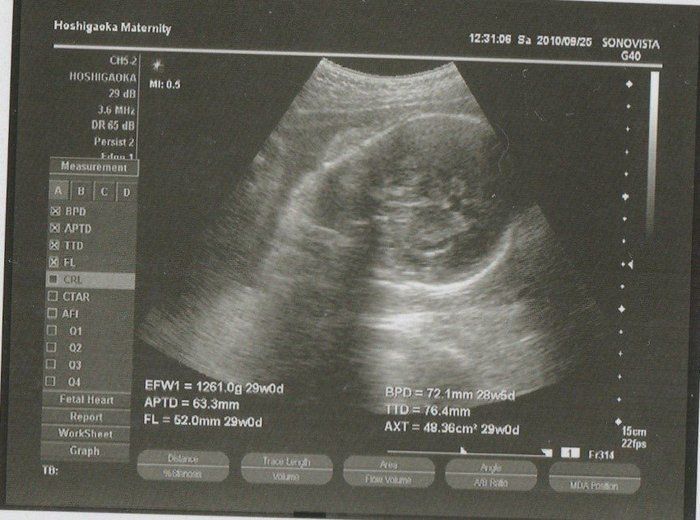

ママにエールさんの妊娠32週目のエコー写真

推定体重1803g。「平均的だから、成長も問題ない」と先生から説明を受けました。赤ちゃんは性別をまだまだ内緒にしているよう。出産も近づきつつあるこの時期、動けるときは運動を兼ねてお散歩したり、劇場などで開かれるランチタイムコンサートなどに行ったりしました。音楽と共に胎動を感じるときは、我が子と一心同体でその瞬間を楽しんでいるような幸せな心地がしました。